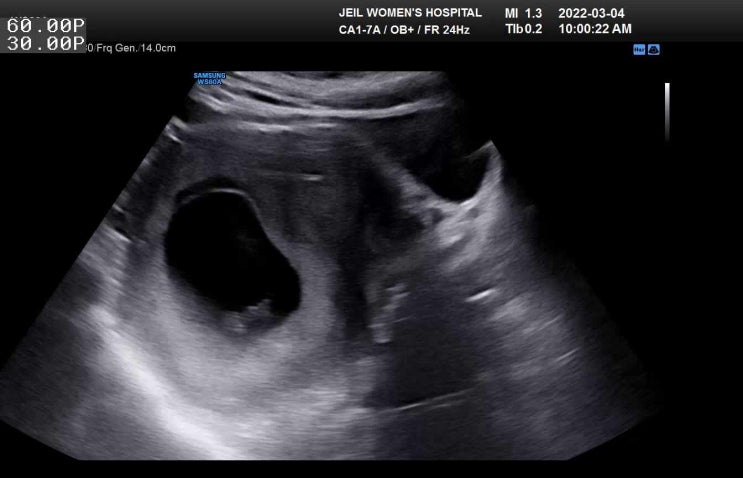

40일 아기 음낭수종,서혜부탈장 수술

38주 3일에 출산 그 후 너무 정신없는 하루하루를 보내다 보니 이제서야 글을 올려 본다.. 노산이라 자연분...